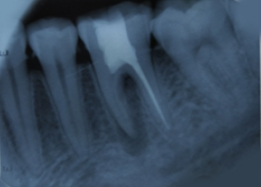

Hemisectomy

Radiograph with Prosthesis (8 Months)